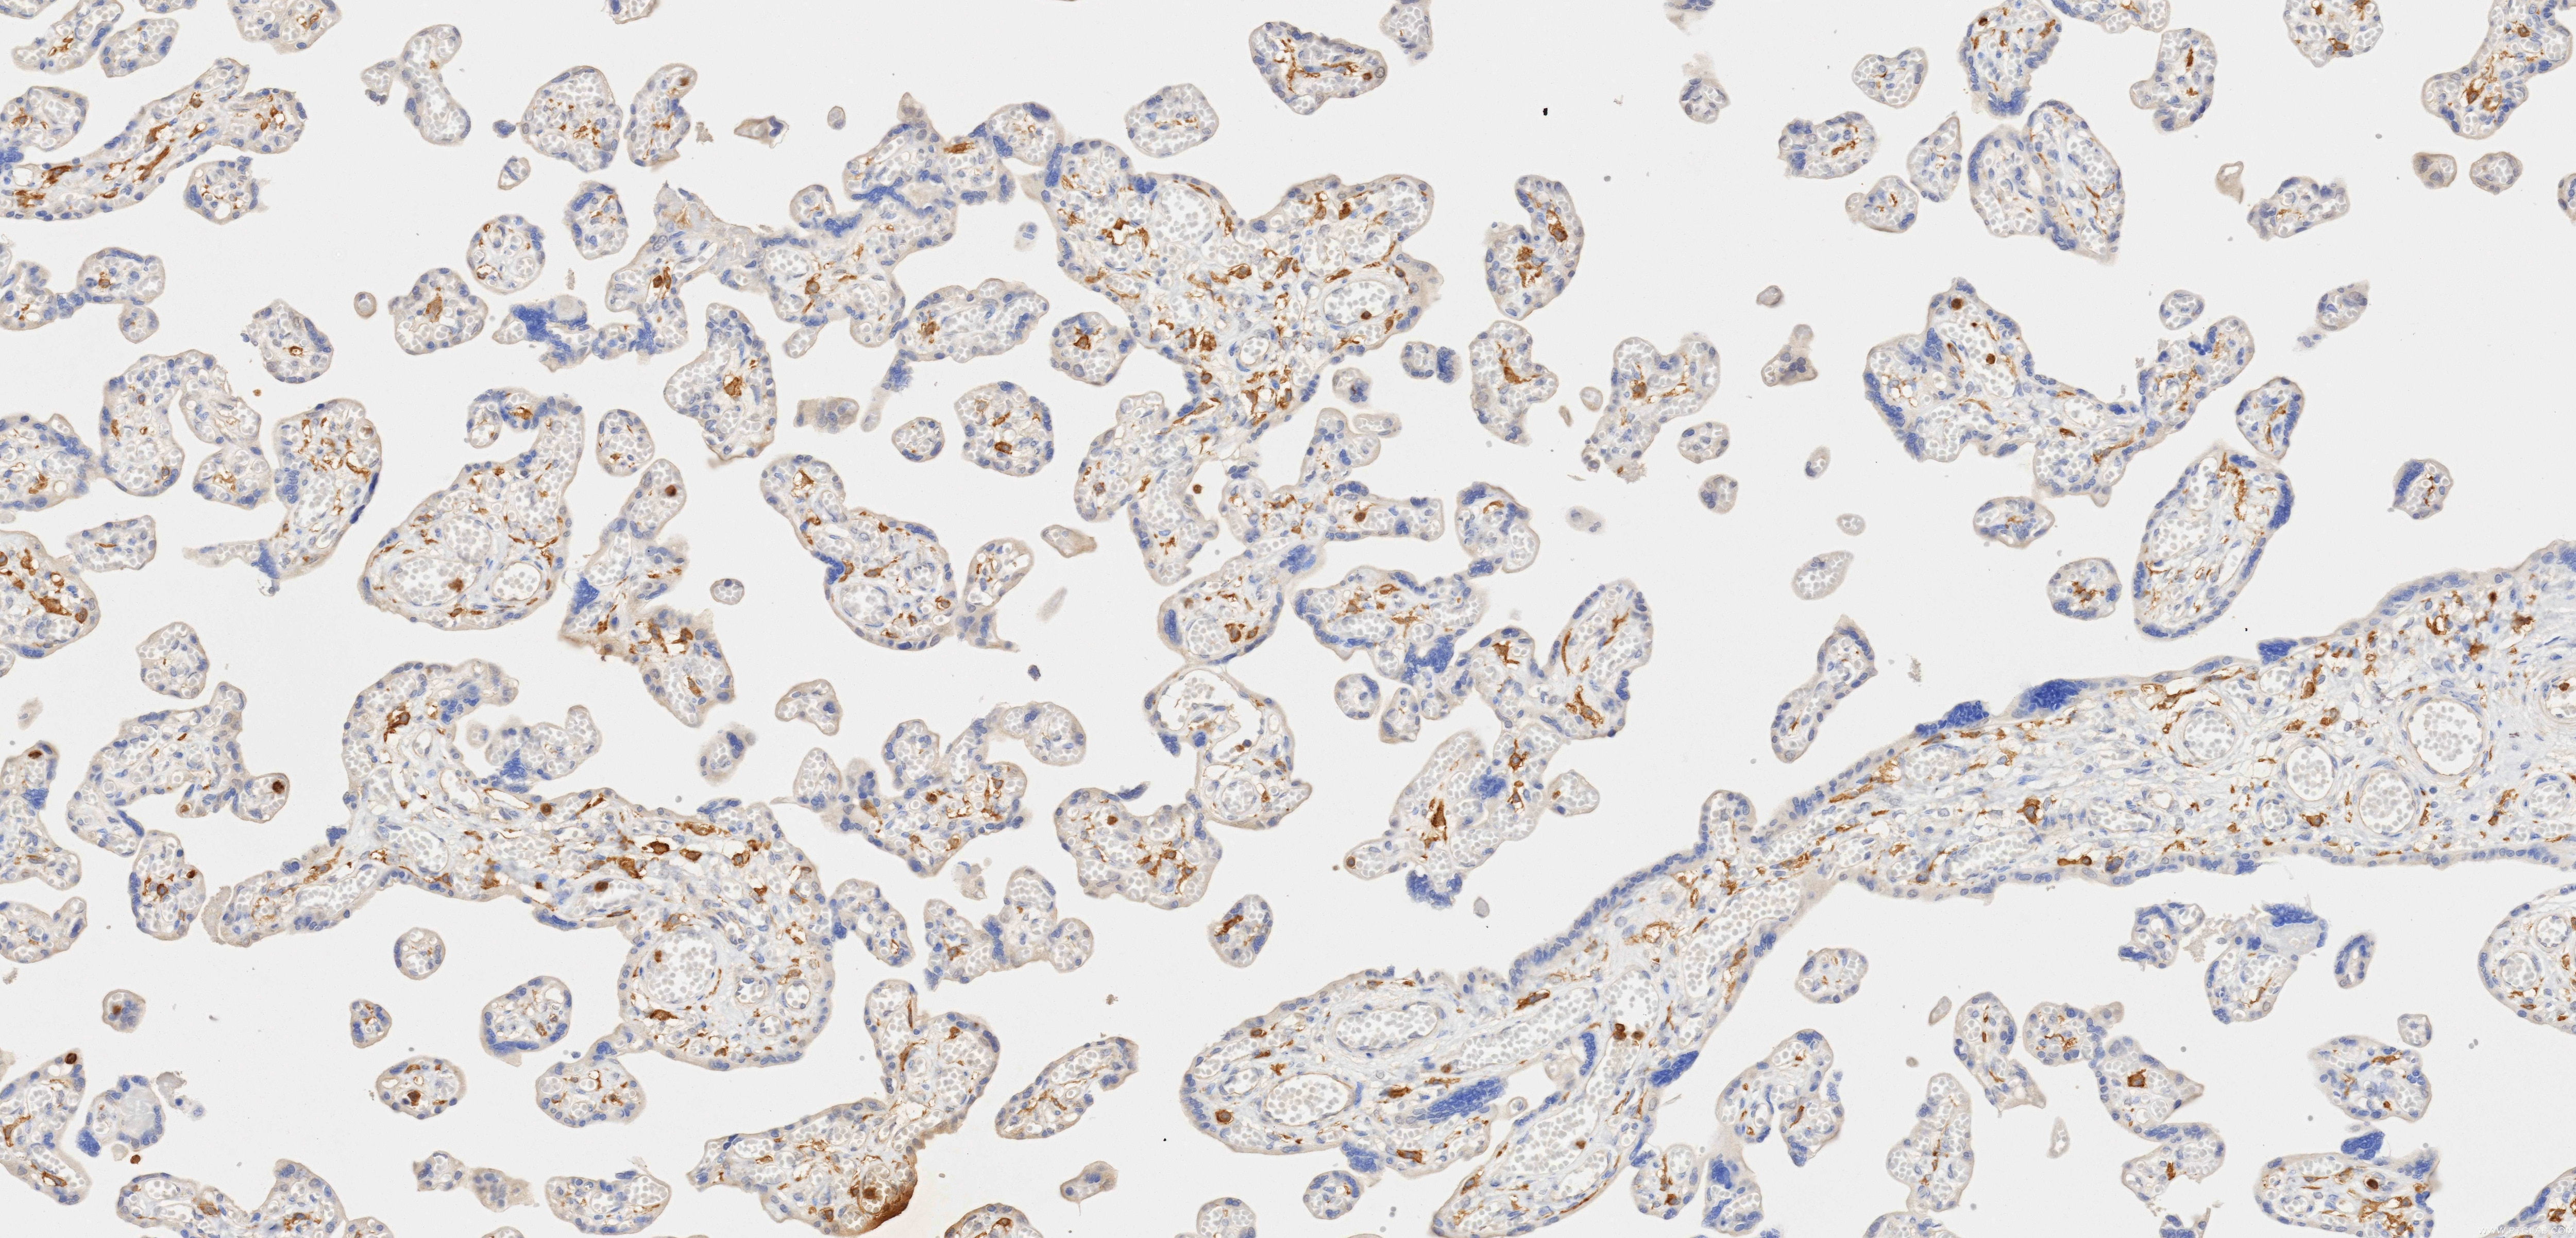

84341-3-PBS targets CD33 in WB, IHC, Indirect ELISA applications and shows reactivity with human samples.